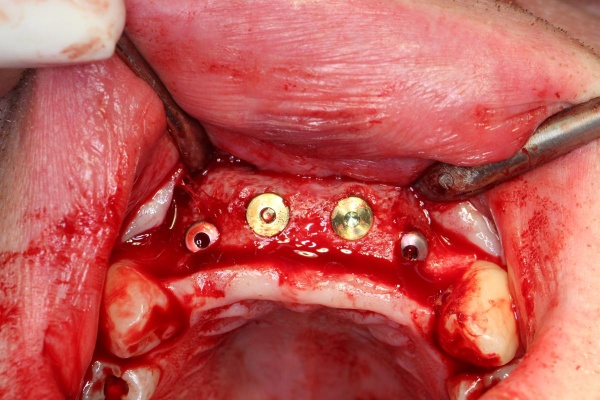

Nach Genehmigung des Antrages erfolgte im März 2012 die Extraktion aller Zähne (Abb. 1).

Im August 2012 erfolgten die 3D-gestützte Implantation (6 Implantate, Firma Nobel Biocare, System Active) im Oberkiefer mit Bone Split sowie eine An- und Auflagerungsosteoplastik vom linken Beckenkamm im Unterkiefer nach Entfernung der Miniimplantate (Abb. 3). Nach komplikationsloser Einheilung wurde im Dezember 2012 die Materialentfernung und Implantation im Unterkiefer (6 Implantate, Firma Nobel Biocare, System Active) durchgeführt (Abb. 4). Die Osseointegration verlief ungestört. Aufgrund der ungenügenden Weichgewebssituation im Unterkiefer erfolgte an jedem Implantat bei Freilegung eine Vestibulumplastik mit Einlagerung einer bioresorbierbaren Membran (Firma Botiss, Mucoderm, Abb. 5 und 6). Die endgültige prothetische Versorgung erfolgte durch den truppenzahnärztlichen Kollegen in der Stammeinheit des Patienten (Zahnarztgruppe Nordholz / SanZ Celle) mit einer gaumenfreien implantatgetragenen Teleskopprothese im Ober- und Unterkiefer, die eine festsitzend-herausnehmbare vollständige stomatognathe Rehabilitation des Patienten ermöglichte (Abb. 7 und 8). Er wurde zum halbjährlichen Recall angehalten.